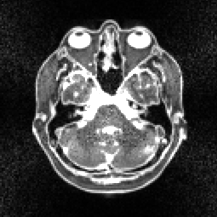

(e) SPDHG 8 coils

100 epochs

Refer to caption

(f) PDHG 8 coils

100 iterations

Figure 1: Images reconstructed using different algorithms. Subfigure (a) shows the original ground truth xsuperscript𝑥x^{\dagger} from which the noisy data samples have been synthetically generated, while subfigure (b) shows a reliable reconstruction xsuperscript𝑥x^{*} to which the other figures should be compared.

Figure 1 shows reconstructions obtained through SPDHG and PDHG. Here, we considered model (19) with squared 2-norm regularizer g(x)=104x2𝑔𝑥superscript104superscriptnorm𝑥2g(x)=10^{-4}\|x\|^{2}. The target solution xsuperscript𝑥x^{*} in (b) has been computed by running SPDHG for large number of epochs (>104absentsuperscript104>10^{4}). Comparing subfigures (e) and (f), the solution for SPDHG seems to be closer to the target (b) than that of PDHG at 100 epochs. At 1,000 epochs, solutions (g) and (h) appear visually similar to each other.